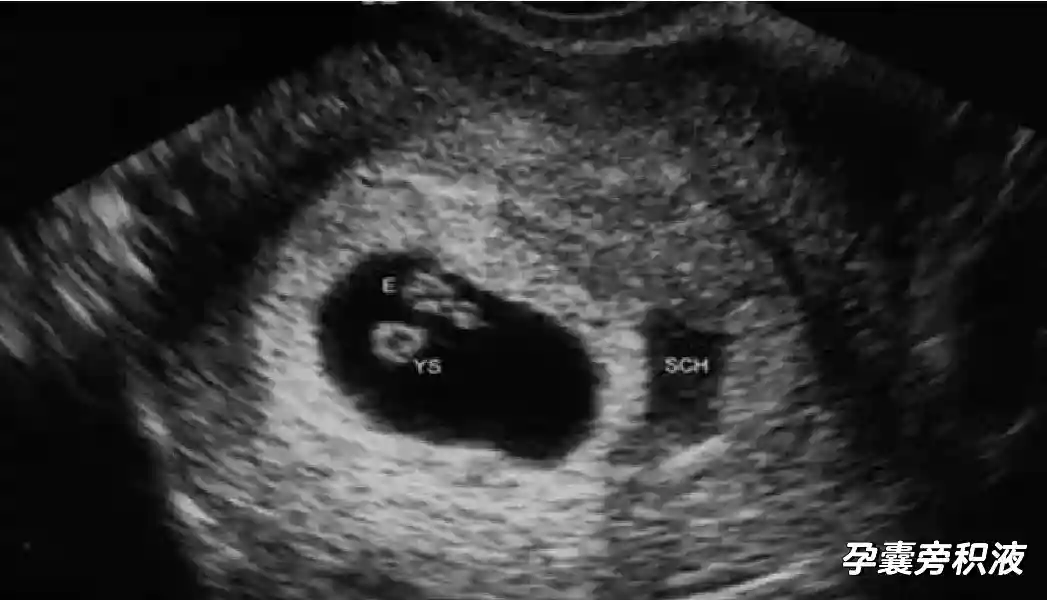

2️⃣卵黄囊:是妊娠囊内第一个解剖结构,直径<7mm。表现为小环状,中央为无回声,囊壁薄,内透声好。卵黄囊位于胚胎旁胚外体腔内。卵黄囊通常在孕5-6周时出现,5-10周稳步增长,一般不超过7mm,至12周消失。妊娠囊的大小与卵黄囊之间有一定关系,妊娠囊平均直径> 8 mm 时,经阴道超声均应显示卵黄囊,妊娠囊平均直径> 18 mm 时,经腹超声均应显示卵黄囊。